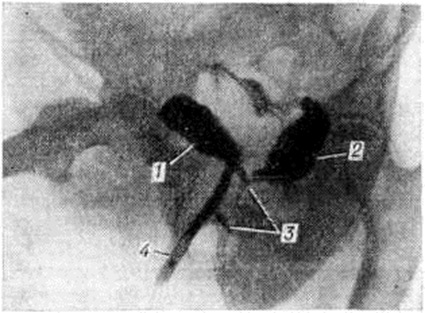

Рис. 2.

Уретроцистограмма больного уретро-простато-ректальным свищом, образовавшимся в результате огнестрельного ранения дробью (указана стрелками): 1 — мочевой пузырь, 2 — прямая кишка, 3 — уретра, 4 — катетер в надлобковом мочепузырном свище.

Уретропростаторектальные свищи возникают вследствие огнестрельных ранений, при операциях на прямой кишке, уретре и после простатэктомии.

Исследование прямой кишки (смотри полный свод знаний Ректороманоскопия), уретроскопия (смотри полный свод знаний) и особенно уретрография, при которой удаётся выявить изменения уретры и затёк контрастного вещества в прямую кишку, подтверждают диагноз (рисунок 2). Изредка уретропростаторектальные свищи закрываются самостоятельно при проведении активной антибактериальной терапии, например, после абсцессов предстательной железы и пролежней при камнях уретры. Оперативное лечение их многоэтапное. Вначале производят цистостомию и наложение противоестественного заднего прохода, затем по стихании воспалительного процесса приступают к основному этапу — закрытию свища. Используют промежностный, брюшно-промежностный и трансректальный доступы. Успеху операции способствуют широкое иссечение свищевого хода и окружающей его рубцовой ткани, мобилизация прямой кишки и уретры для смещения на разные уровни мочевого и калового отрезков свища, раздельное ушивание прямой кишки и уретры, а также использование лоскута из мышечной ткани, вводимого между мочевым пузырём и прямой кишкой. Применяют лоскуты на ножке из большой ягодичной мышцы, нежной мышцы бедра или волокна мышцы, поднимающей задний проход. При успехе операции через 2—3 месяцев удаляют дренаж из мочевого пузыря, а затем восстанавливают проходимость кишечника.